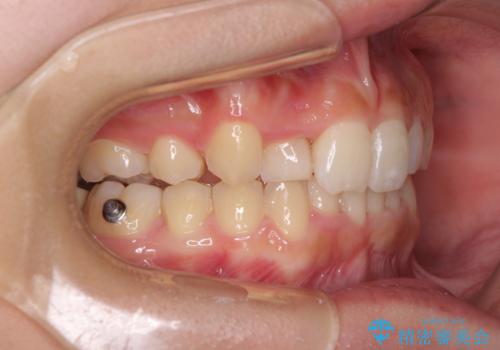

- 上顎の重なっている前歯を気にして来院された患者様です。

八重歯改善には抜歯が必要で、八重歯の移動量が多く、更には右側にずれている正中を改善する必要がありました。

インビザライン単体での治療は困難と判断し、補助装置により八重歯移動後にインビザラインを用いることとしました。

インビザラインでは治療期間が延びることが予想されたため、ワイヤー矯正を提案しましたが、セラミッククラウンが多く、壊すあるいは傷が付く可能性があることから、長期間であってもインビザラインを選択されました。